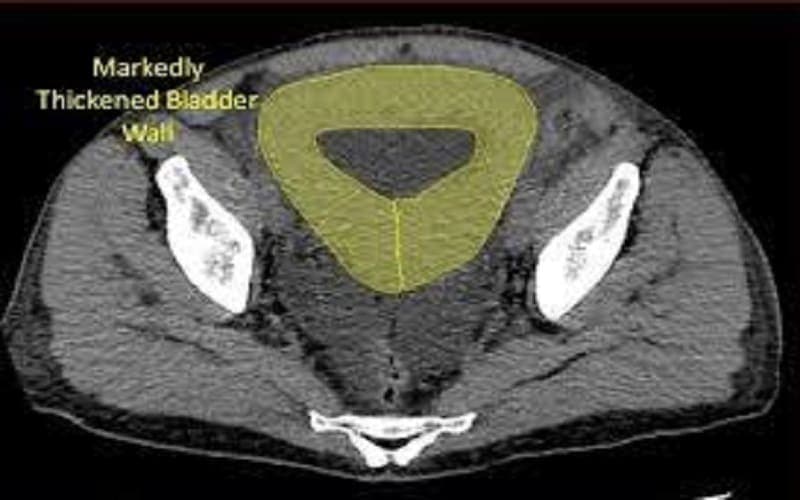

Dày thành bàng quang xảy ra khi bàng quang phải hoạt động nhiều hơn để đẩy nước tiểu ra ngoài, khiến lớp cơ của bàng quang dày lên. Tình trạng này có thể xuất hiện khu trú ở một vùng hoặc dày toàn bộ thành bàng quang. Trong nhiều trường hợp, đây là dấu hiệu liên quan đến các bệnh lý của hệ tiết niệu như viêm nhiễm, tắc nghẽn đường tiểu hoặc khối u.

Thành bàng quang dày 5mm có sao không còn tùy thuộc vào tình trạng bàng quang khi thực hiện chẩn đoán hình ảnh. Nếu bàng quang chưa căng đầy nước tiểu, thành bàng quang có thể trông dày hơn bình thường và dễ gây ra kết quả dày giả. Tuy nhiên, nếu bàng quang đã căng đầy mà thành bàng quang vẫn dày khoảng 5mm thì đây có thể là dấu hiệu bất thường và cần được kiểm tra thêm.

Ngoài độ dày, bác sĩ cũng đánh giá hình thái dày của thành bàng quang để xác định nguyên nhân. Nếu thành bàng quang dày lan tỏa và tương đối đồng đều, nguyên nhân thường liên quan đến các vấn đề chức năng như bàng quang phải co bóp nhiều do tắc nghẽn đường tiểu, sỏi bàng quang, phì đại tuyến tiền liệt hoặc do viêm nhiễm. Ngược lại, nếu chỉ dày khu trú ở một vùng, đây có thể là dấu hiệu đáng chú ý hơn vì có khả năng liên quan đến khối u hoặc tổn thương tại chỗ.